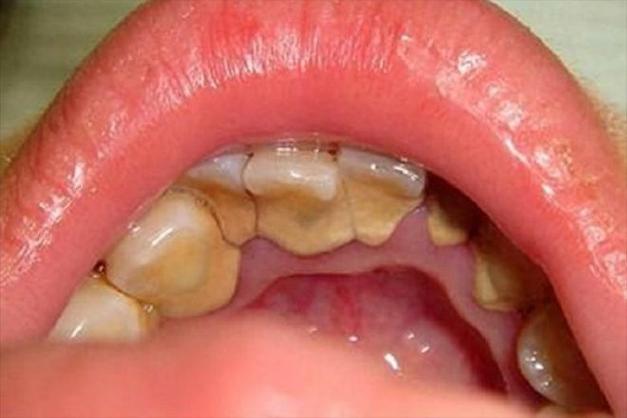

它是什么? 这些黄颗粒,通常是牙菌斑和食物残渣的混合物,经过唾液中的矿物质(钙、磷等)沉积后,形成的软垢或牙结石的雏形,它们常常藏匿在牙齿与牙龈的交界处(牙龈沟)、牙缝、牙齿的咬合面以及舌头上。

为什么是黄色? 牙菌斑本身是无色的,但它会大量繁殖,并和我们在饮食中摄入的色素(如茶、咖啡、酱油、烟草等)结合,久而久之就形成了黄色或黄褐色的沉积物。

如何判断? 通常在刷牙前或早晨刚起床时最为明显,用指甲轻轻刮一下,会发现这些物质可以被刮掉,并伴有轻微的出血或异味,这是身体在提醒你:“嘿,该认真刷牙了!”